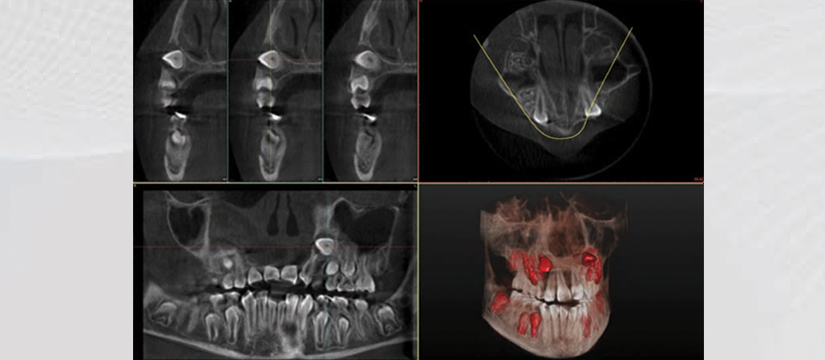

- Sinus Exam

- 3D Sinus Positioning